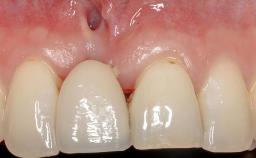

Soft-Tissue Volume Augmentation Using a Connective-Tissue Graft Harvested from the Maxillary Tuberosity

In 1983, a 51-year-old non-smoking patient was referred for the treatment of moderate chronic periodontitis. At the initial examination, 47% of sites exhibited probing depths of 4 to 6 mm. Periodontal therapy consisted of initial periodontal treatment including oral-hygiene instructions and supra- and subgingival debridement, followed by periodontal surgery to eliminate residual pockets.